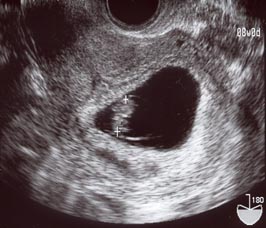

またですよ…(8w6dくらい)

2006/07/06 (Thu) - 妊娠初期(~15w)

今日は出勤するつもりだったのになぁ…(おいおい)。

お化粧途中でもよおしてトイレへ…

したらば!

また茶色のオリモノさんご降臨!!

おなかもちょっと痛いような気がするのでお休みしました。

しかし、どうして病院が休みの木曜に出血したりするんだろう…。

酷くならないように祈るしかないっすね…。

母子手帳貰ってきました。

2006/06/30 (Fri) - 妊娠初期(~15w)

今日は仕事を休んで(とにかくできるだけ退職前に有給を使いたい一心・笑)

お約束の検診に行ってきました。

で!晴れて8週に入ったらしく、妊娠証明書を貰ってきました。